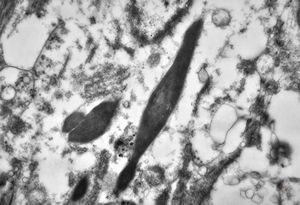

M, 43y. | myeloid leukemia … Auer bodies

M, 43y. | myeloid leukemia … Auer bodies

M, 43y. | myeloid leukemia … Auer bodies